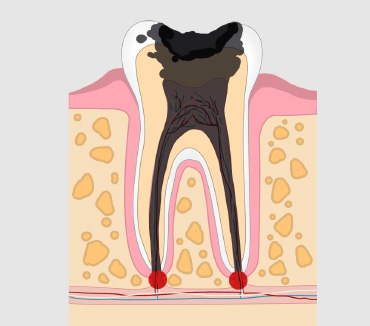

什么是智齿蛀牙?

智齿发炎即智齿冠周炎,智齿冠周炎是一种发生在第三磨牙周围软组织的炎症。智齿冠周炎通常是由于智齿萌出不足、细菌感染等原因引起。

智齿蛀牙的危害

轻度龋齿患者的牙齿对某些刺激性食物过敏。严重龋病患者不仅会影响其外观,还会导致牙髓炎、冠周炎和严重牙痛。